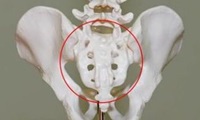

주말에 티비채널을 돌리다가 상어연골을 주제로 다룬 프로를 보게되었는데 콘드로이친에 대한 언급이 많더라고요. 그래서 오늘은 콘드로이친 효능 및 콘드로이친 1200mg 권장량에 대해 알아보는 시간을 가지려고 합니다. 콘드로이친 이름이 참 생소하죠? 그리스어로 콘드로스라는 것에서 유래되었다고 하는데 연골이라는 뜻을 가지고 있습니다. 사람의 몸을 지지해주는 지지대역할을 하는 곳 사이사이에 들어있어요. 척추뼈의 중간쯤 미끌거리고 말랑한 부분으로 생각하면 될 것 같네요.

우리몸의 뼈 중간마디를 구성하는 중요한 성분인 연골은 우리 몸 안에 수분다음으로 많은 비중을 차지하고 있습니다. 연골의 구조이자 뼈대의 역할인 중요 성분으로 각광받고있는 글루코사민과 함께 사람들의 건강을 책임지고 있는데요.